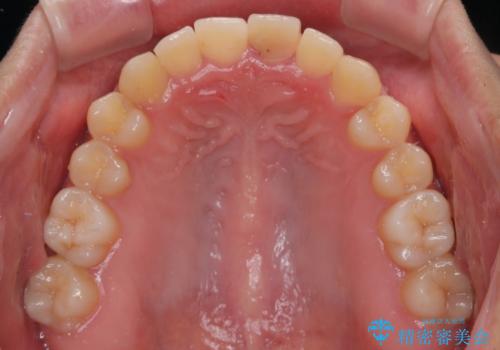

長い間歯肉が炎症を患っていたため、炎症改善後には歯肉がやや退縮した状態となっていました。

歯肉移植により歯肉形態を改善するプランも提案しましたが、十分な仕上がりとのことで、大変満足していただけました。